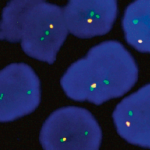

Quick Order Quick Order Name Email Address Company Address Catalog Number Quantity Message 14 + 11 = Submit Category Blocking Reagents Both Counterstain Country International US Detection Kit Detection Kit Detection kit 1-Step Polymer Kit Detection Kits - IHC 1-Step Polymer HRP Kits IHC AP Detection Kit IHC HRP Detection Kit IHC Mouse on Mouse 1-step Poly HRP kit New & Improved 1-Step Polymer HRP Kit IHC New & Improved Polymer HRP Kits IHC Polymer HRP Kits IHC Rapid Polymer HRP Kits IHC Double Staining eFISH Detection Kits ISH-Detection Kits Multiplex Detection Kits New & Improved Detection Kits Polymer HRP Kits IHC eFISH Enzymes for Tissue Processing Enzymes for Tissue Processing i6000 and Manual Instruments ISH Probes ISH-Detection Systems Links / Labels items-Manual Microscope Microchamber Slides & Coverslips for Xmatrx Microscope Slides & Accesories for i6000 and Manual Microscope Slides & Accessories Microscope Slides & Accessories miRNA Probes Primary Antibodies A Antibody Cocktail B C D E F G H I J K L M N O P R S T U V W Y Z Reagents Antigen Retrieval Solutions Blocking Reagents Blocking Reagents Buffers and Diluents Buffers eFSH Buffers ISH Buffers Counter Stains Detection Kit Dewaxing & Rehydration Reagents Diagnostic Antigen Retrieval Solutions eFISH Antigen Retrieval Solutions ISH Blocking Reagents ISH Enzymes Mounting Media eFISH Mount Media Nucleic Acid Retrieval Substrates & Chromogens ISH DAB replacements Slide Labels Vials Immunohistochemistry In situ Hybridization eFISH eFISH Probes eFISH Visualization Kits eFISH Visualization Kit Cyto eFISH Visualization Kit Histo Visualization Kit Ancillaries & Consumables Consumable Kits IHC Consumable Kits ISH Consumable Kits Counterstain and Mounting Media Counterstain Mounting PAP Pen Pipette Tips Reagent Vials & Accessories Reagent Vials & Accessories for i6000TM Diagnostics Reagent Vials & Accessories for Open system Automation Reagent Vials & Accessories for Xmatrx Elite Reagnet vials and accessories-1 Automation Detection Systems miRNA ISH Multiplexing & Double Staining Filters Sort results Reset Apply Double Staining Kit Rabbit AP Mouse HRP Biogenex Select 100 tests60 tests500 tests Buy here EBER Probe Select Probes - 25 tests - manualProbes - 25 tests - XmatrxElite Buy here EBER Probe Select Probes - 25 tests - manualProbes - 25 tests - XmatrxElite Buy here eFISH 13/CEN 18/21 Triple Color Probe Select 10 tests (RTU)20 tests (RTU) Buy here eFISH 13/CEN 18/21 Triple Color Probe Select 10 tests (RTU)20 tests (RTU) Buy here eFISH 19q13/19p13 Dual Color Probe Select 10 tests (RTU)20 tests (RTU) Buy here eFISH 19q13/19p13 Dual Color Probe Select 10 tests (RTU)20 tests (RTU) Buy here eFISH 1p12 Probe Select 10 tests (RTU)20 tests (RTU) Buy here eFISH 1p36/1q25 Dual Color Probe Select 10 tests (RTU)20 tests (RTU) Buy here eFISH 1p36/1q25 Dual Color Probe Select 10 tests (RTU)20 tests (RTU) Buy here ‹ 1 … 76 77 78 … 146 ›